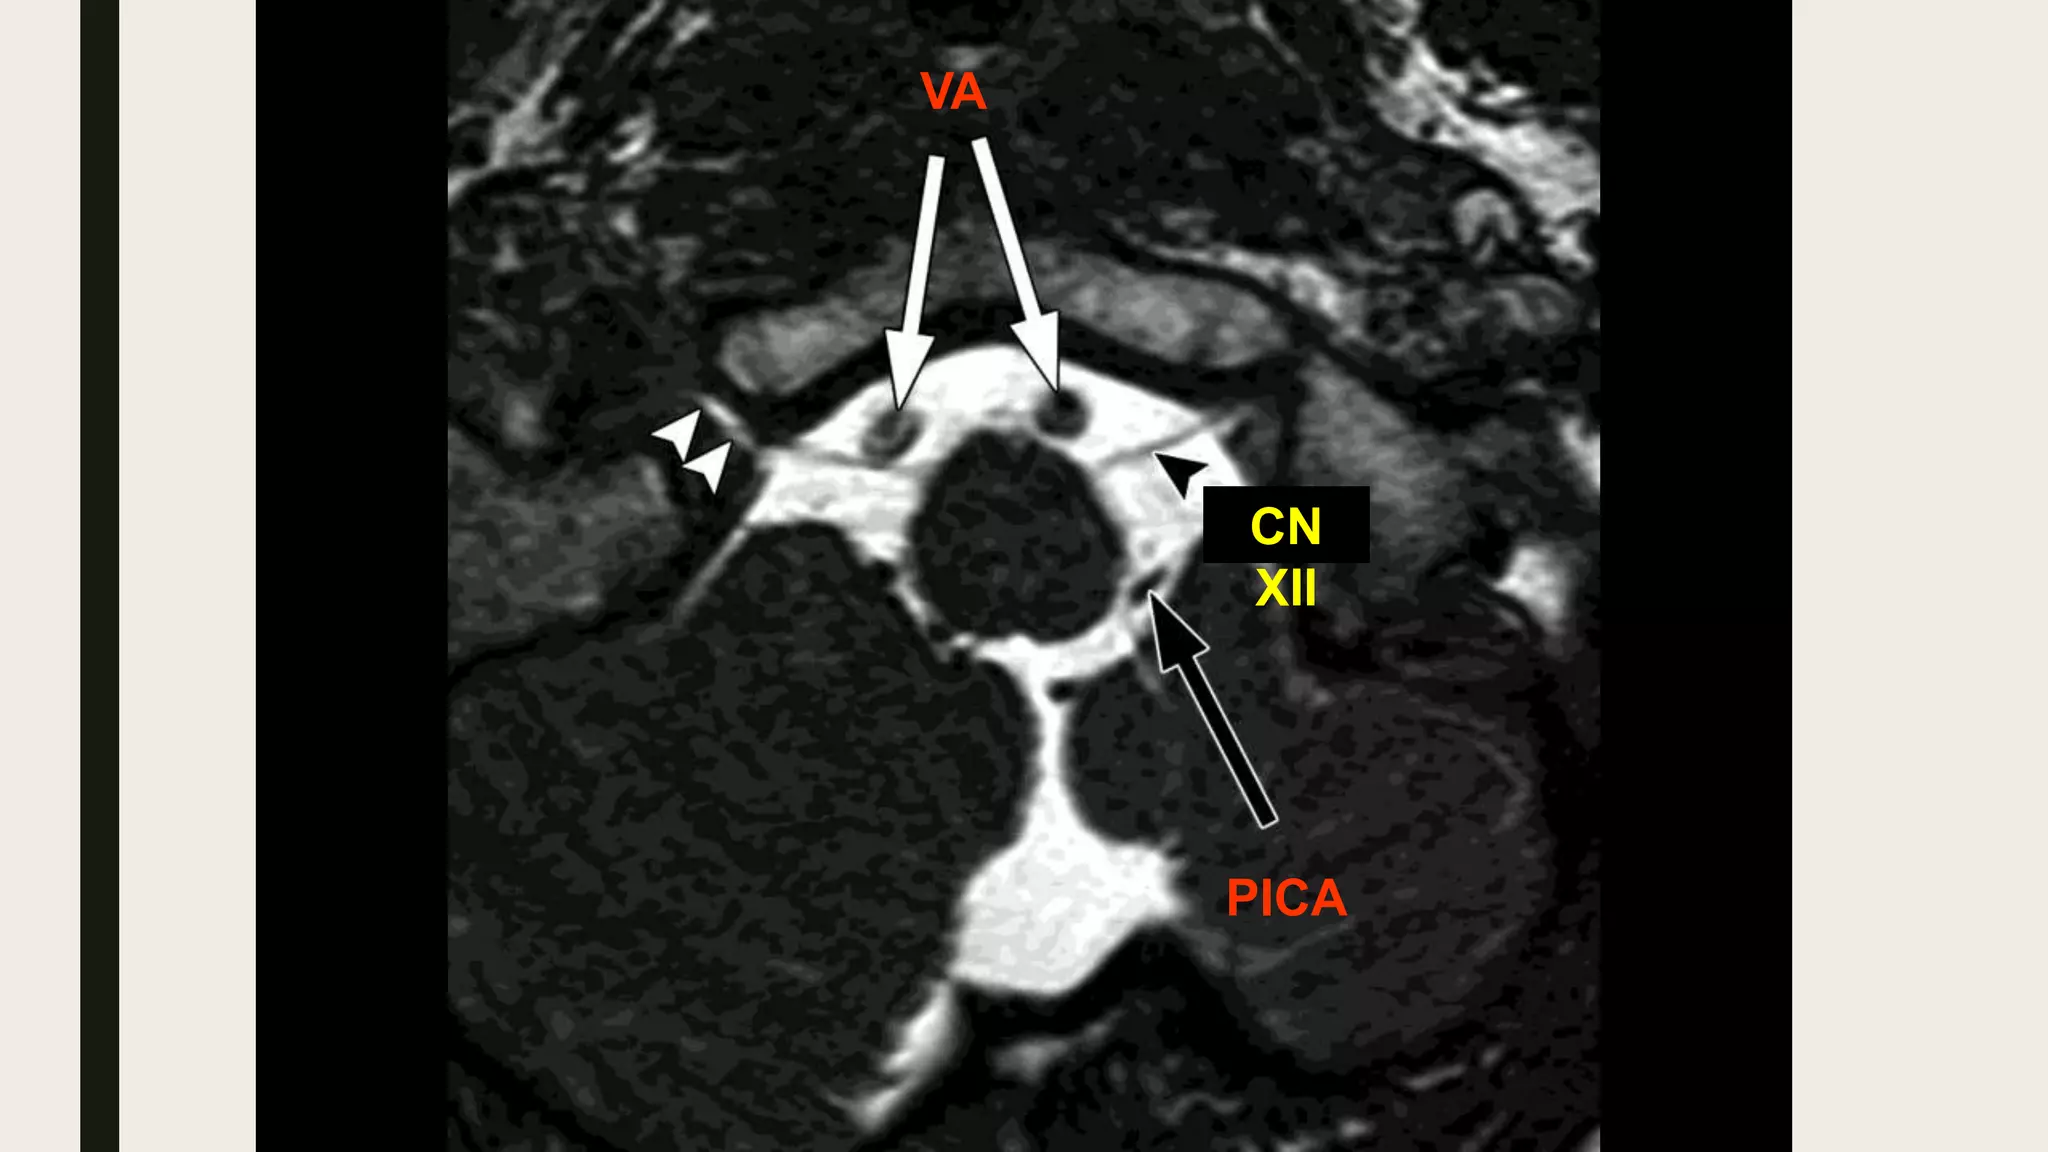

Premedullary (Medullary) cistern

• Anterior to the medulla.Location

• Vertebral arteries.

• PICA.

• Anterior spinal artery.

• Posterior spinal arteries.

• Pre-medullary V.

• CN XII.

Contents

Medullary cistern

PICA

CN

XII

VA